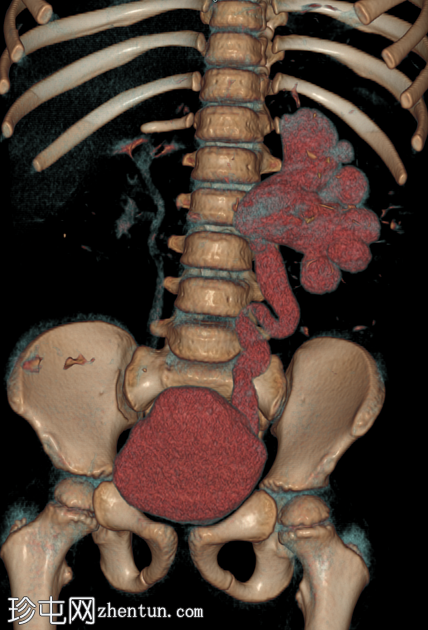

冠状位增强CT(延迟期)

在这张多期增强CT图像中,我们可以观察到肾盏、肾盂以及左侧输尿管全程扩张。

未见感染或其他相关征象。

本例为原发性巨输尿管。整个泌尿系统的扩张是诊断的关键。